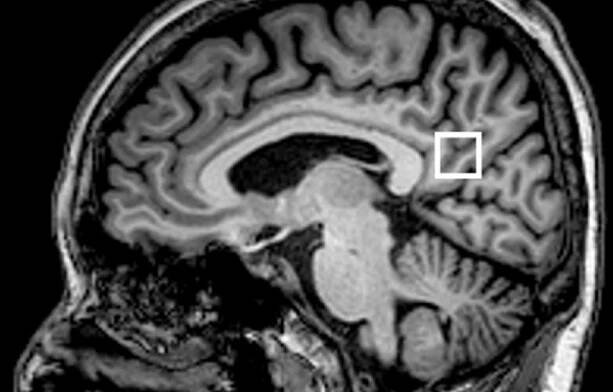

Nádory mozku nebo také intrakraniální nádory jsou takové nádory, které postihují mozek a mozkové obaly (mozkové pleny). Může se jednat jak o nádory primární, tedy o nádory vzniklé přímo z příslušných tkání, tak i o nádory sekundární, tedy…

Nádor mozku, někdy též nesprávně označovaný jako rakovina mozku, je ročně diagnostikován přibližně 700 – 800 pacientům v České republice. Představuje asi 1,5 % ze všech zhoubných nádorových onemocnění.